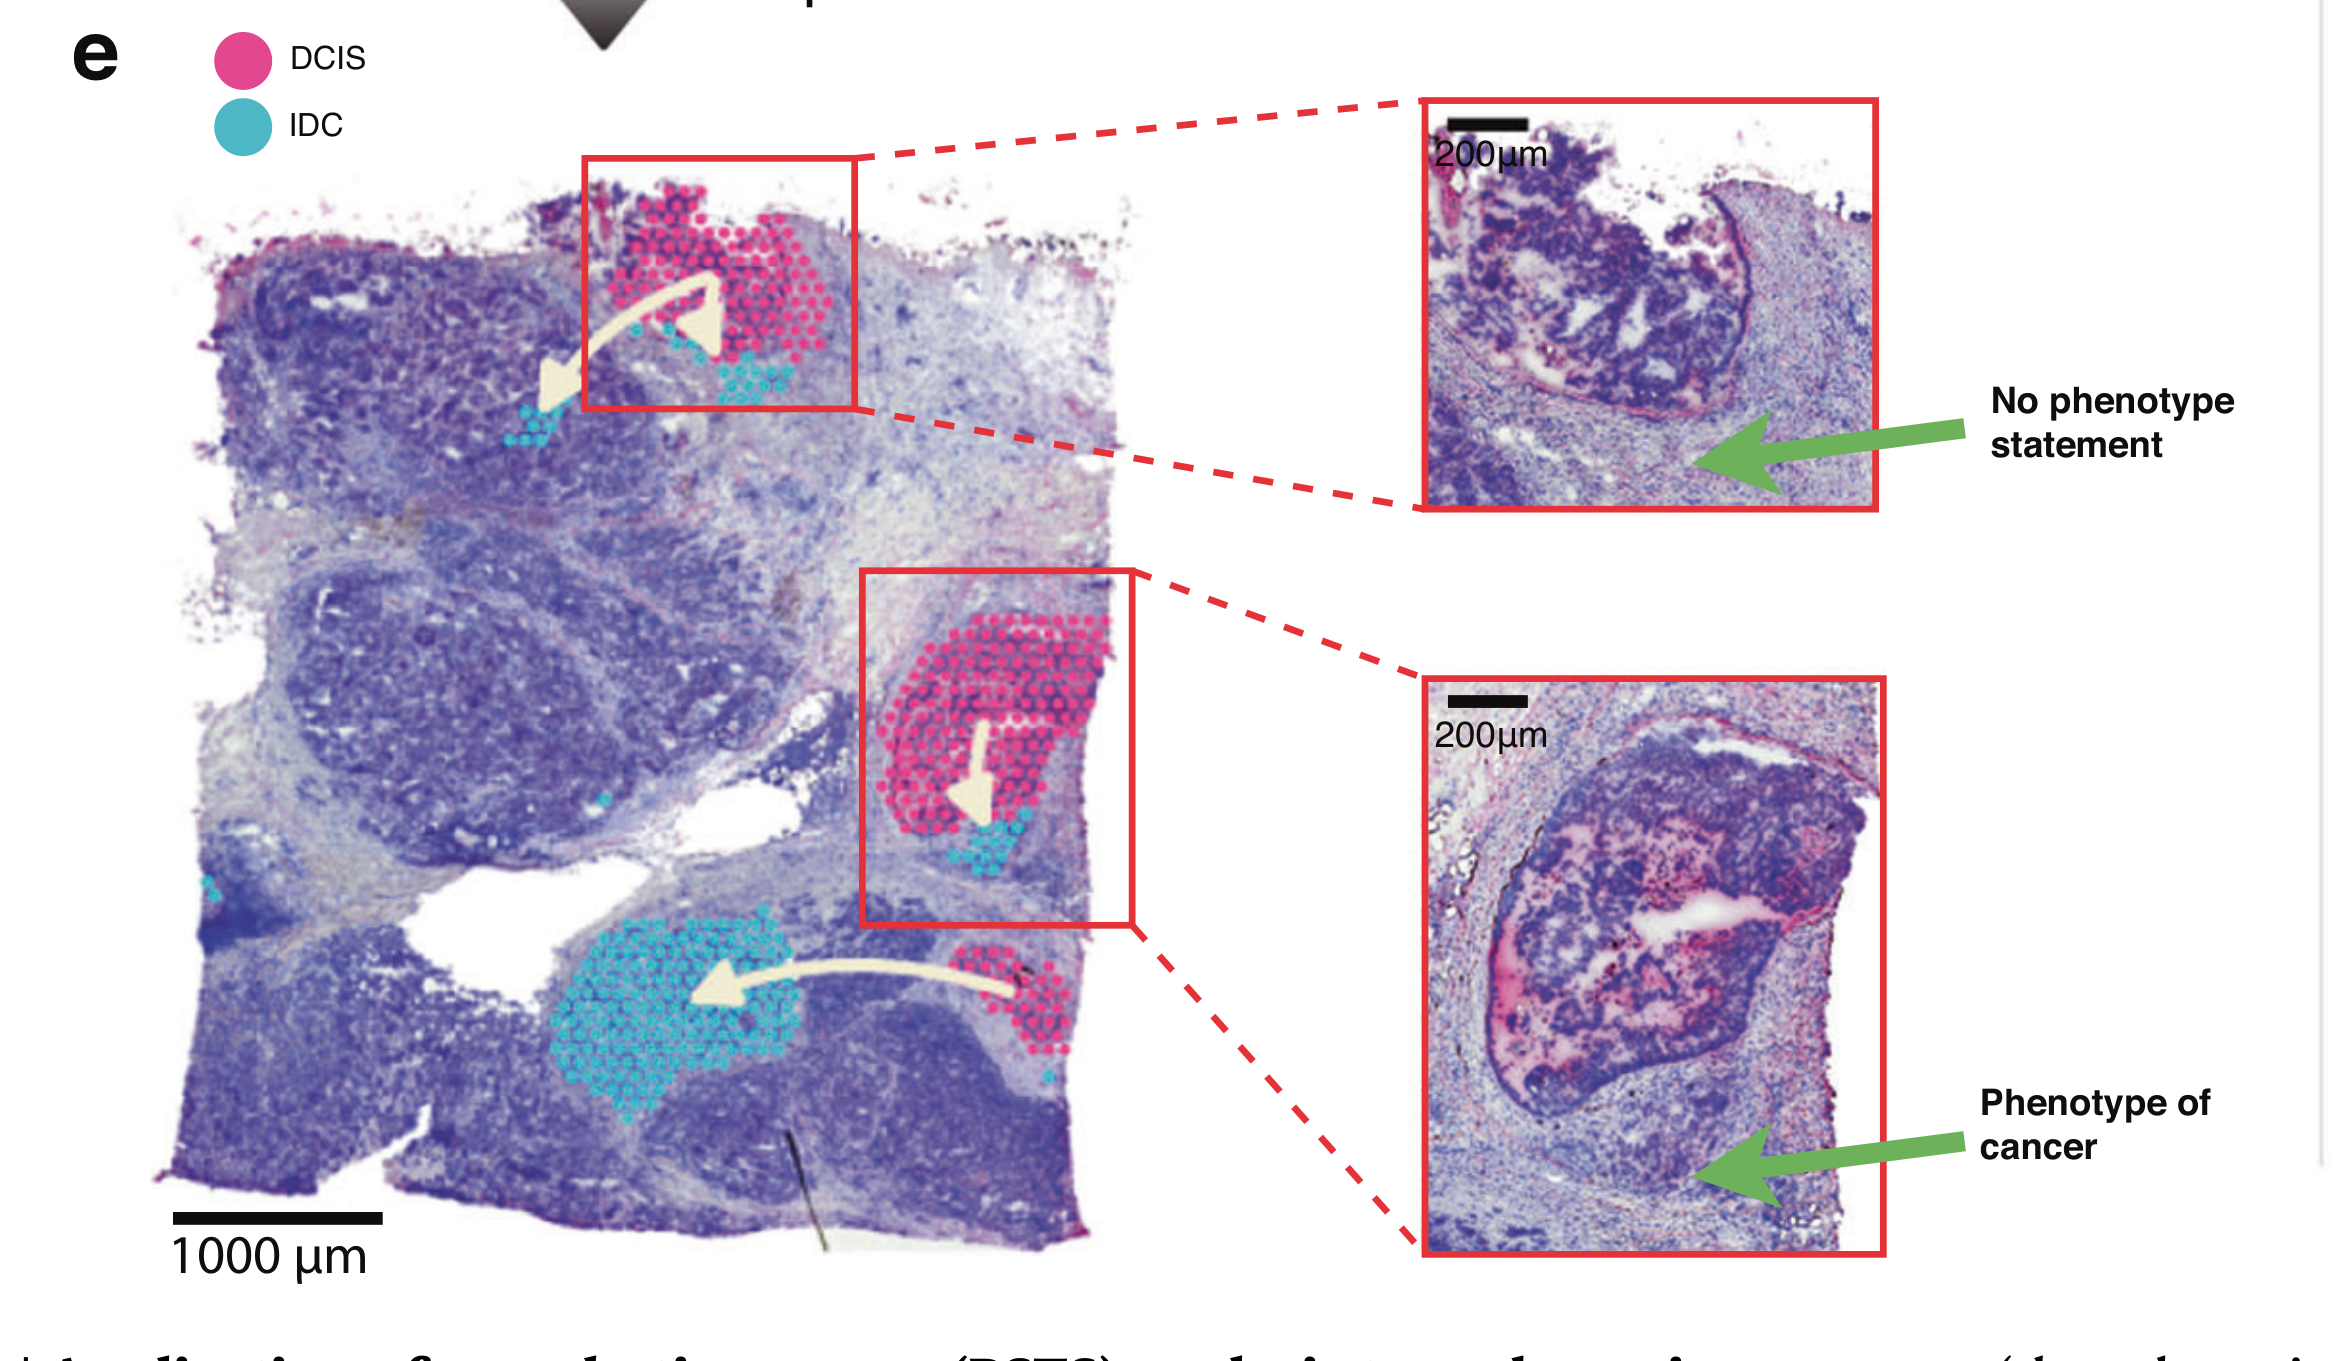

Where are tumor regions located within the spatial architecture of a tissue section?

Hägele et al., 2024

Visual Compositional Data Analytics for Spatial Transcriptomics